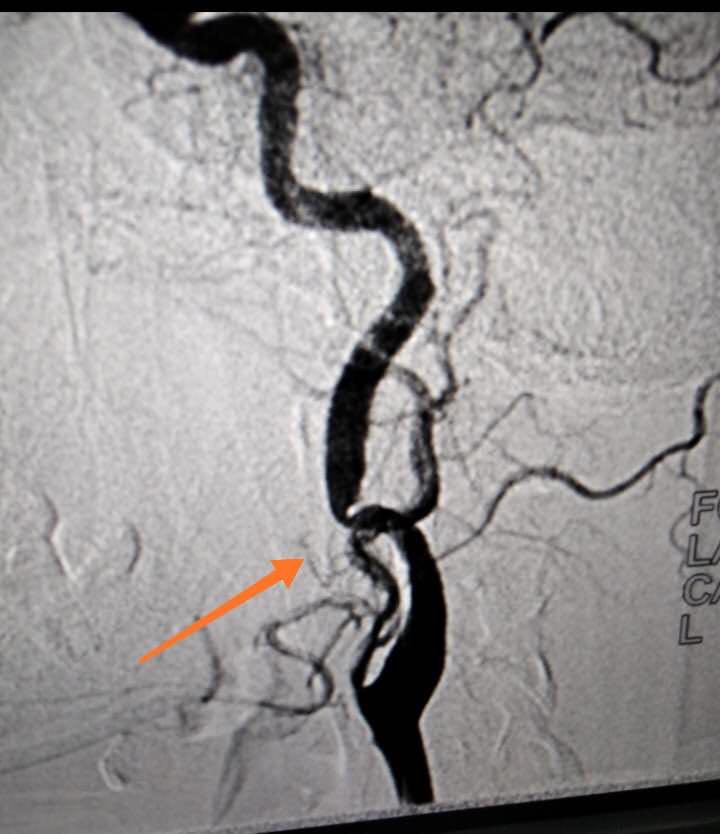

患者青年女性,發(fā)作性頭暈多年,輾轉(zhuǎn)各地醫(yī)院進(jìn)行診治,均未明確具體原因。經(jīng)我院給予全腦血管造影術(shù),發(fā)現(xiàn)病變血管,明確病因,為以后的診治確立了正確的方向。首次開展此項(xiàng)檢查,對(duì)我們醫(yī)護(hù)人員是一個(gè)重大考驗(yàn),從術(shù)前準(zhǔn)備到成功完成檢查再到術(shù)后護(hù)理,我們醫(yī)護(hù)人員能夠熟練掌握流程,嚴(yán)格遵守各項(xiàng)操作規(guī)范,使患者快速有效完成檢查?;颊弑硎緦?duì)治療效果很滿意。

全腦血管造影術(shù)是在數(shù)字減影血管造影(DSA)系統(tǒng)的支持下,采用血管內(nèi)導(dǎo)管操作技術(shù),通過(guò)選擇性造影、栓塞、擴(kuò)張成形、機(jī)械清除、藥物遞送等具體方法,對(duì)累及人體神經(jīng)血管系統(tǒng)的病變進(jìn)行診斷和治療。它是一種微創(chuàng)臨床技術(shù),為許多腦與脊髓血管疾病開辟了新的思路和治療途徑。既可以獨(dú)立解決許多腦血管疾病,又可以和傳統(tǒng)的開放手術(shù)、放射治療等巧妙結(jié)合,使原來(lái)無(wú)法或難以治療的疾病得到滿意療效。它不但能提供病變的確切部位,而且可以清楚地了解病變的范圍、嚴(yán)重程度、與周圍血管的關(guān)系等細(xì)節(jié),對(duì)確立治療方案指導(dǎo)進(jìn)一步治療有重要意義。